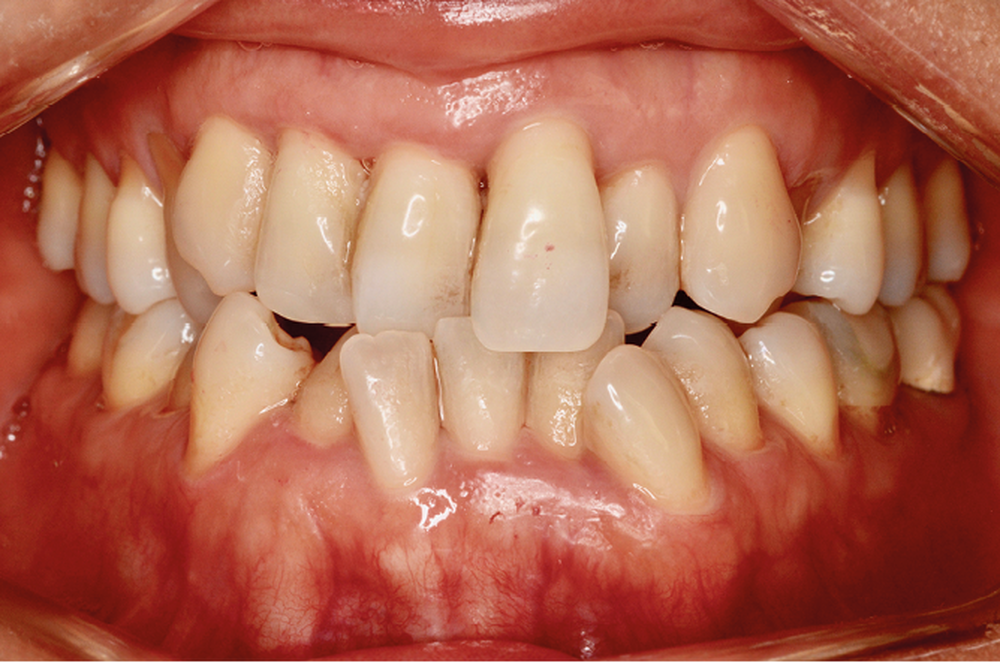

Mme J. présente une face longue, un profil droit avec un angle naso-labial fermé, une birétrocheilie et un menton bien dessiné. La ligne du sourire est basse, avec un sourire denté exposant peu les dents maxillaires, mais avec un parallélisme entre la lèvre inférieure et les bords libres des incisives maxillaires assez harmonieux.

Sur le plan squelettique, on retrouve une classe III de Ballard par hypomaxillie, dans un schéma facial hyperdivergent.

Sur le plan dentaire, la patiente est en classe III droite et gauche, canine et molaire de 6 mm, avec une occlusion inversée antérieure localisée à 11, 12 et 22. Elle présente une dysharmonie dents-arcades sévère, une agénésie d’une incisive mandibulaire est à signaler, et les troisièmes molaires ont été extraites à l’âge de 21 ans.

Au niveau fonctionnel, on note un bruxisme statique avec contact permanent entre les dents maxillaires et mandibulaires. La patiente présente des prématurités en relation centrée sur les incisives, le guidage en propulsion est perturbé et des interférences multiples sont retrouvées en latéralités droite et gauche.